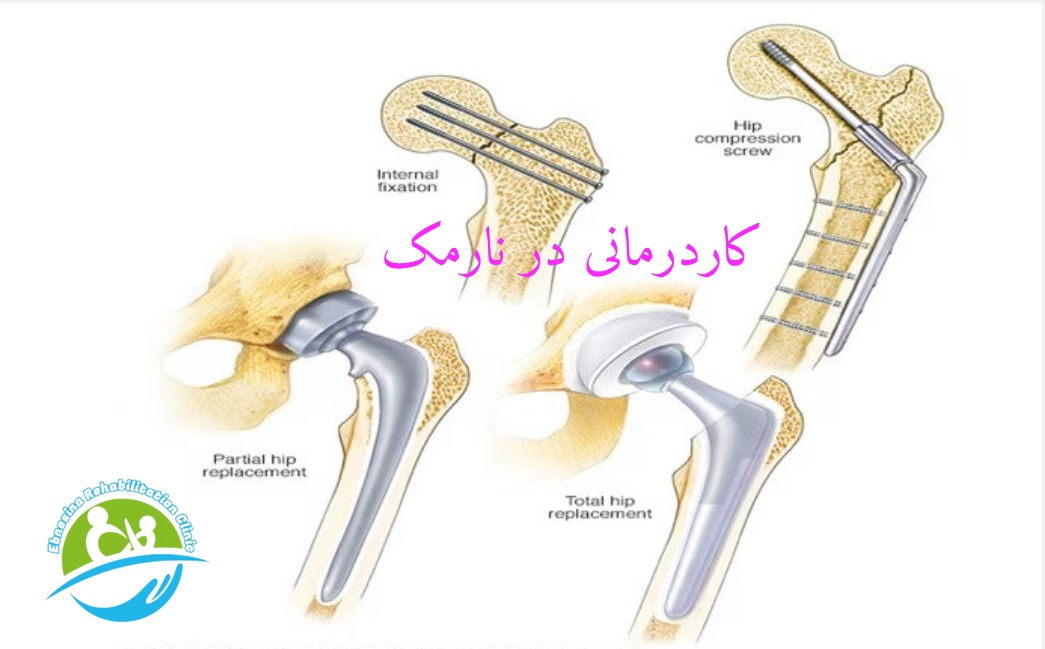

نوع جراحی عموماً به محل و شدت شکستگی و اینکه آیا استخوانهای شکسته به درستی تراز نشدهاند یا خیر، بستگی دارد. سن و بیماریهای زمینهای شما نیز در این امر نقش دارند. گزینهها عبارتند از:

ترمیم داخلی با استفاده از پیچ. پیچهای فلزی در استخوان قرار داده میشوند تا در حین بهبودی شکستگی، آن را در کنار هم نگه دارند. گاهی اوقات پیچها به یک صفحه فلزی که از استخوان ران عبور میکند، متصل میشوند.

تعویض کامل مفصل ران. قسمت بالای استخوان ران و حفره در استخوان لگن با قطعات مصنوعی به نام پروتز جایگزین میشوند. مطالعات به طور فزایندهای نشان میدهند که تعویض کامل مفصل ران در بزرگسالان سالم که به طور مستقل زندگی میکنند، مقرون به صرفهتر است و با نتایج بلندمدت بهتری همراه است.

تعویض جزئی مفصل ران. در برخی شرایط، نیازی به تعویض قسمت حفره مفصل ران نیست. تعویض جزئی مفصل ران ممکن است برای بزرگسالانی که بیماریهای دیگری دارند یا دیگر به طور مستقل زندگی نمیکنند، توصیه شود.